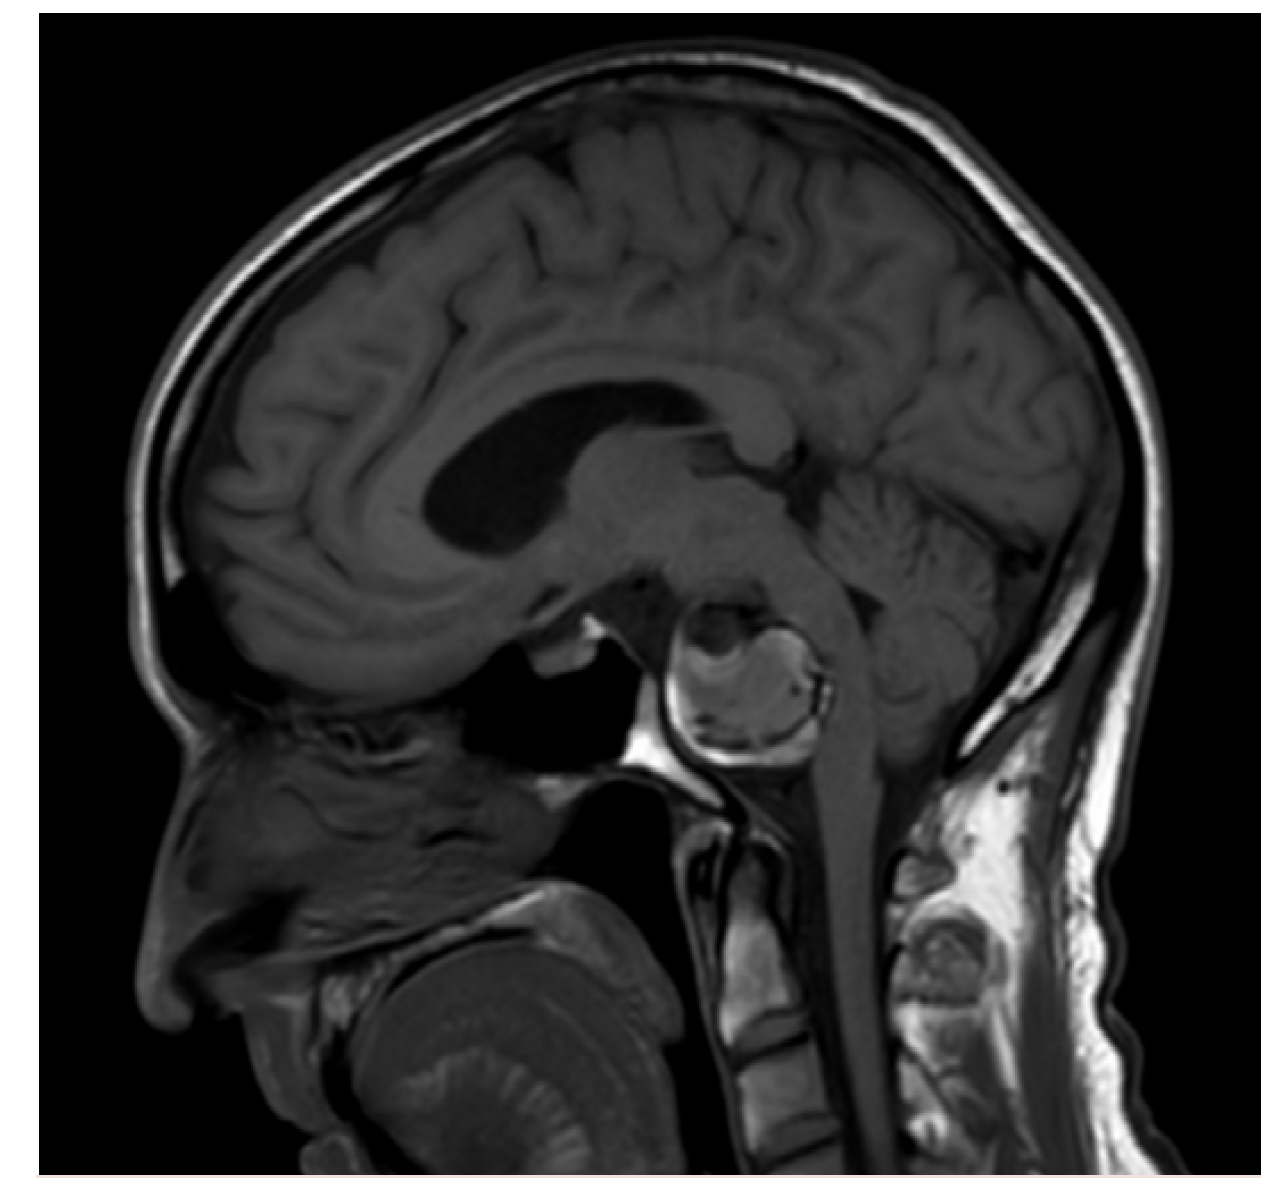

In the first case, a healthy 59-year-old patient presented to the ER with aneurysmal subarachnoid hemorrhage and an unusual ruptured right internal carotid artery dorsal wall aneurysm (Figure 6). While each practice approaches these somewhat differently, this is a flow diversion case for Goodman Campbell Brain and Spine.